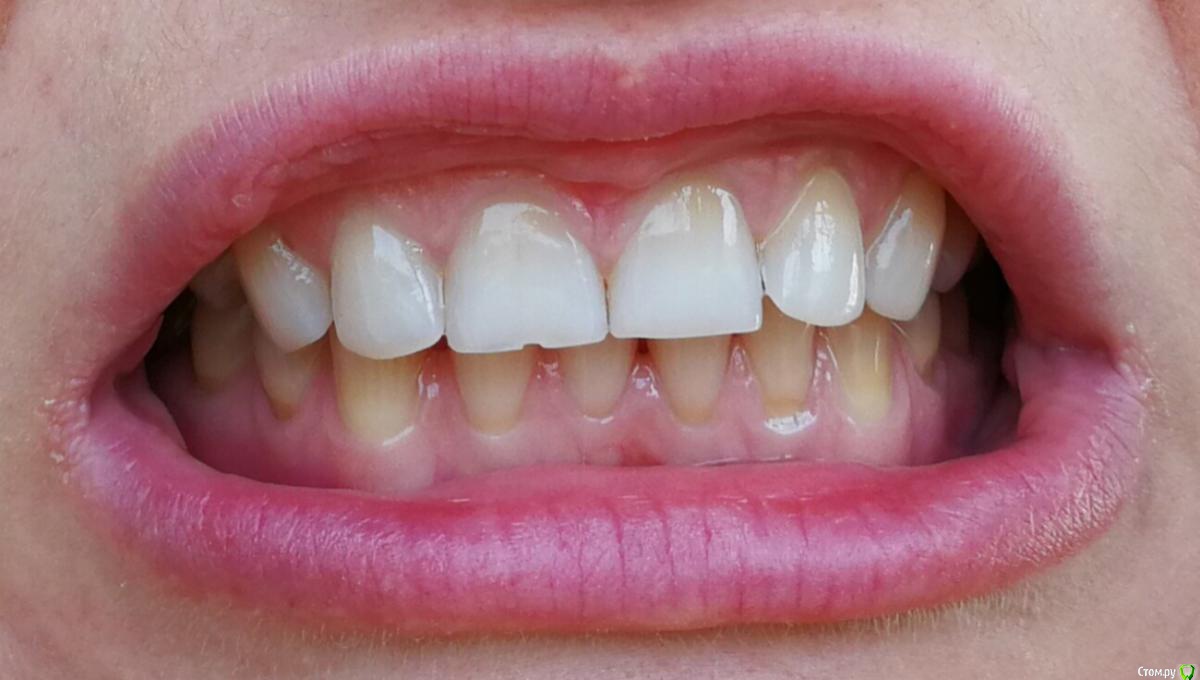

Ольга2000 Опубликовано 27 октября, 2019 Поделиться Опубликовано 27 октября, 2019 Здравствуйте. Мне 37 лет, ничего не беспокоит, нет повышенной чувствительности, кровоточивости. Мне кажется, что такие зубы у меня были последних лет 10, т.е. каких то изменений я не замечала.Делая последний раз гигиену ротовой полости врач сказала, что ей не нравится мой прикус. Через некоторое время я открывала зубами лекарство (понимаю, что так нельзя) и откололся кусочек переднего зуба. Это и подтолкнуло к записи к врачу.Первый врач осмотрел, сделал фотографии и сказал, что надо поднимать прикус с помощью пломб, пломбировать оголённые шейки зубов и ещё на отбеливание записал.Вчера была на приёме у ортодонта. Сделал снимок, сказал что с прикусом ничего не надо делать, посоветовал проконсультироваться с пародонтологом, т.к. поднимается кость. Я не знаю что мне делать. У меня следующие вопросы: 1. Надо ли поднимать прикус?2. Надо ли пломбировать оголение шеек зубов?3. На 11 и 21 зубах бороздки. Что с ними делать?4. Может капу на ночь сделать, чтобы зубы не стирались?5.И вообще что мне надо делать в обязательном порядке? И в необязательном тоже. Спасибо за ответы. Ссылка на комментарий

krokomot Опубликовано 27 октября, 2019 Поделиться Опубликовано 27 октября, 2019 По вашим фотографиям не возможно сказать нужно ли вам поднимать прикус, скорее всего да, слевой стороны у вас стираемость зубов, зубы попадают бугор на бугор, есть смещение центральной линии. также с левой стороны 6й зуб визуально не в очень хорошем состоянии. нужно ли вам что то делать? вы должны решить сами, зубы слева на буграх сточены до дентина, то есть эмаль уже полностью стерта далее с течением времени зубы начнут изнашиваться всё быстрее и быстрее. наличие полосок на нижних зубах можно не пломбировать, а скорректировать чистку зубов перейдя на выметающие движения , а не горизонтальные. если вы хотите еще 37 лет прожит со своими собственными зубами и не испытывать проблем, то нужно пройти ортодонтическое лечение и восстановить анатомию стертых зубов керамикой. Это остановит стираемость, а можете это сделать через 10 лет, но объем вмешательства возрастет кратно... 1 Ссылка на комментарий